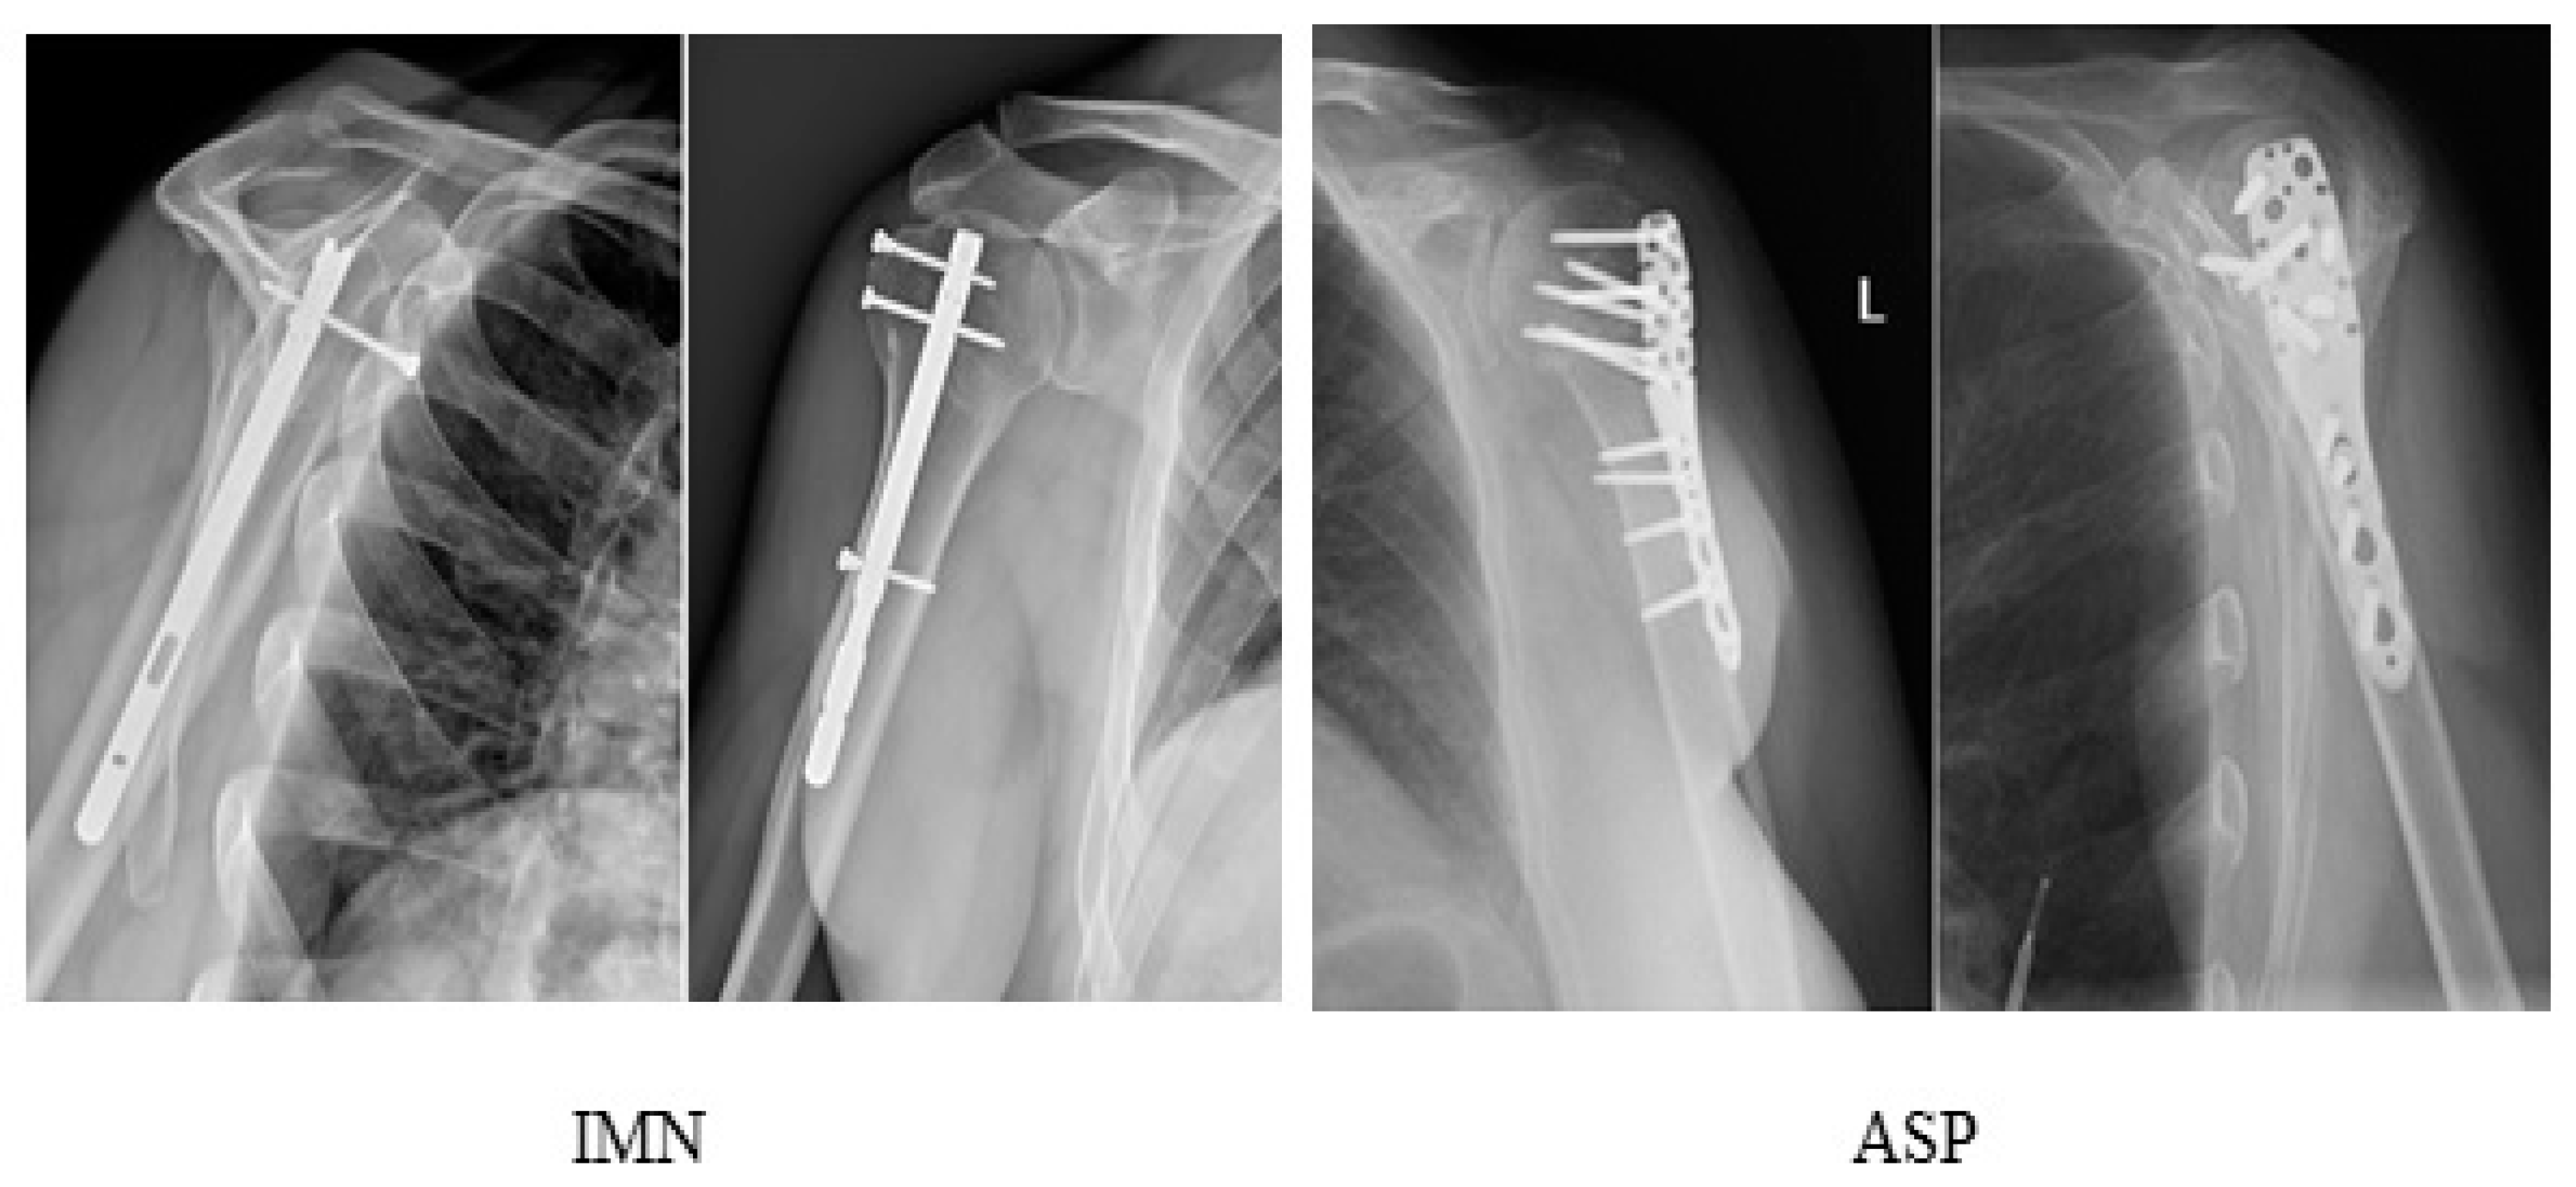

Stabilization of Comminuted Fractures of the Proximal Humerus with Intramedullary Nails and Angularly Stable Locking Plates—Functional Results before and during the SARS-COVID-19 Pandemics

2. Materials and Methods